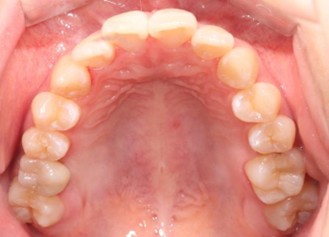

20代 男性

治療前

治療後

治療後- リスク・副作用

(薬・注射・レントゲン・CT・データ分析・骨造成・サージカルステント・血液検査・仮歯) - 年齢/性別

- 20代/男性

- 患者の具体的な症状

- 1年前に左上12 右上1の根の治療をし、その後放置していたら、左上2が破折した。

左上2インプラント補綴 左上1右上1オールセラミック装着。

歯根破折と虫歯による痛み、審美障害を主訴として来院。 - 検査方法

- コーンビームCT、レントゲン撮影

- 診断結果

- 左上2 歯根破折

- 治療詳細

- 左上抜歯後、インプラント埋入1本

骨造成あり 局所麻酔

インプラント治療後、左上1右上1セラミック修復2本 - 通院回数